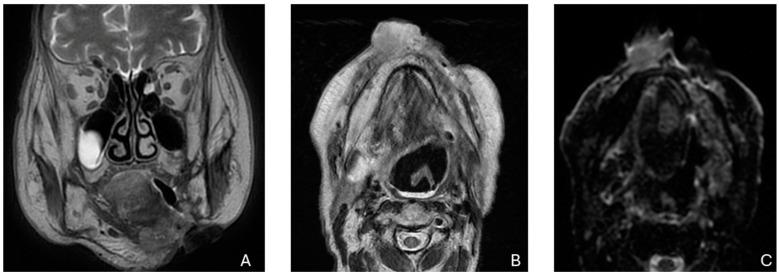

Squamous cell carcinoma of the head and neck (SCCHN) is among the ten most common cancers worldwide, with advanced SCCHN presenting with a 5-year survival of 34% in the case of nodal involvement and 8% in the case of metastatic disease. Disease-free survival at 2 years is 67% for stage II and 33% for stage III tumors, whereas 12-30% of patients undergo distant failures after curative treatment. Previous treatments often hinder the success of salvage surgery and/or reirradiation, while the standard of care for the majority of metastatic SCCHN remains palliative chemo- and immuno-therapy, with few patients eligible for locoregional treatments. The aim of this paper is to review the characteristics of recurrent SCCHN, based on different recurrence sites, and metastatic disease; we will also explore the possibilities not only of salvage surgery and reirradiation but also systemic therapy choices and locoregional treatment for metastatic SCCHN.

头颈部鳞状细胞癌(SCCHN)是全球十大常见癌症之一,晚期头颈部鳞状细胞癌若出现淋巴结受累,其5年生存率为34%,若出现转移性疾病则为8%。II期肿瘤的2年无病生存率为67%,III期肿瘤为33%,而12 - 30%的患者在接受根治性治疗后会出现远处转移。既往治疗常常会妨碍挽救性手术和/或再次放疗的成功实施,而大多数转移性头颈部鳞状细胞癌的标准治疗方案仍是姑息性化疗和免疫治疗, eligible for locoregional treatments, eligible for locoregional treatments,符合局部区域治疗条件的患者很少。本文旨在基于不同的复发部位和转移性疾病,对头颈部鳞状细胞癌复发的特征进行综述;我们还将探讨转移性头颈部鳞状细胞癌的挽救性手术、再次放疗、全身治疗选择以及局部区域治疗的可能性。 (注:最后一句原文中“eligible for locoregional treatments”重复了两遍,推测可能有误,但按照要求不添加解释,保留原文翻译。)